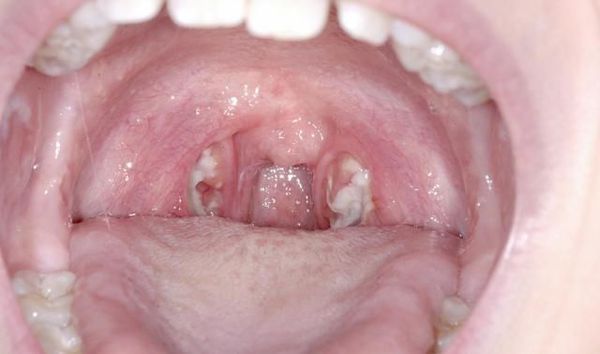

- катаральна (почервоніння і набряк мигдаликів);

Мигдалики набряклі, червоного кольору («соковиті»), що відповідає катарального тонзиллиту. Зазвичай цю стадію захворювання не розпізнають (не встигають) і яскрава візуалізація настає на другу добу захворювання, коли в тканини мигдалин утворюються фолікули білого кольору, розмірами 2-3 мм, що підносяться над поверхнею тканини мигдалин — розвивається фолікулярний тонзиліт.